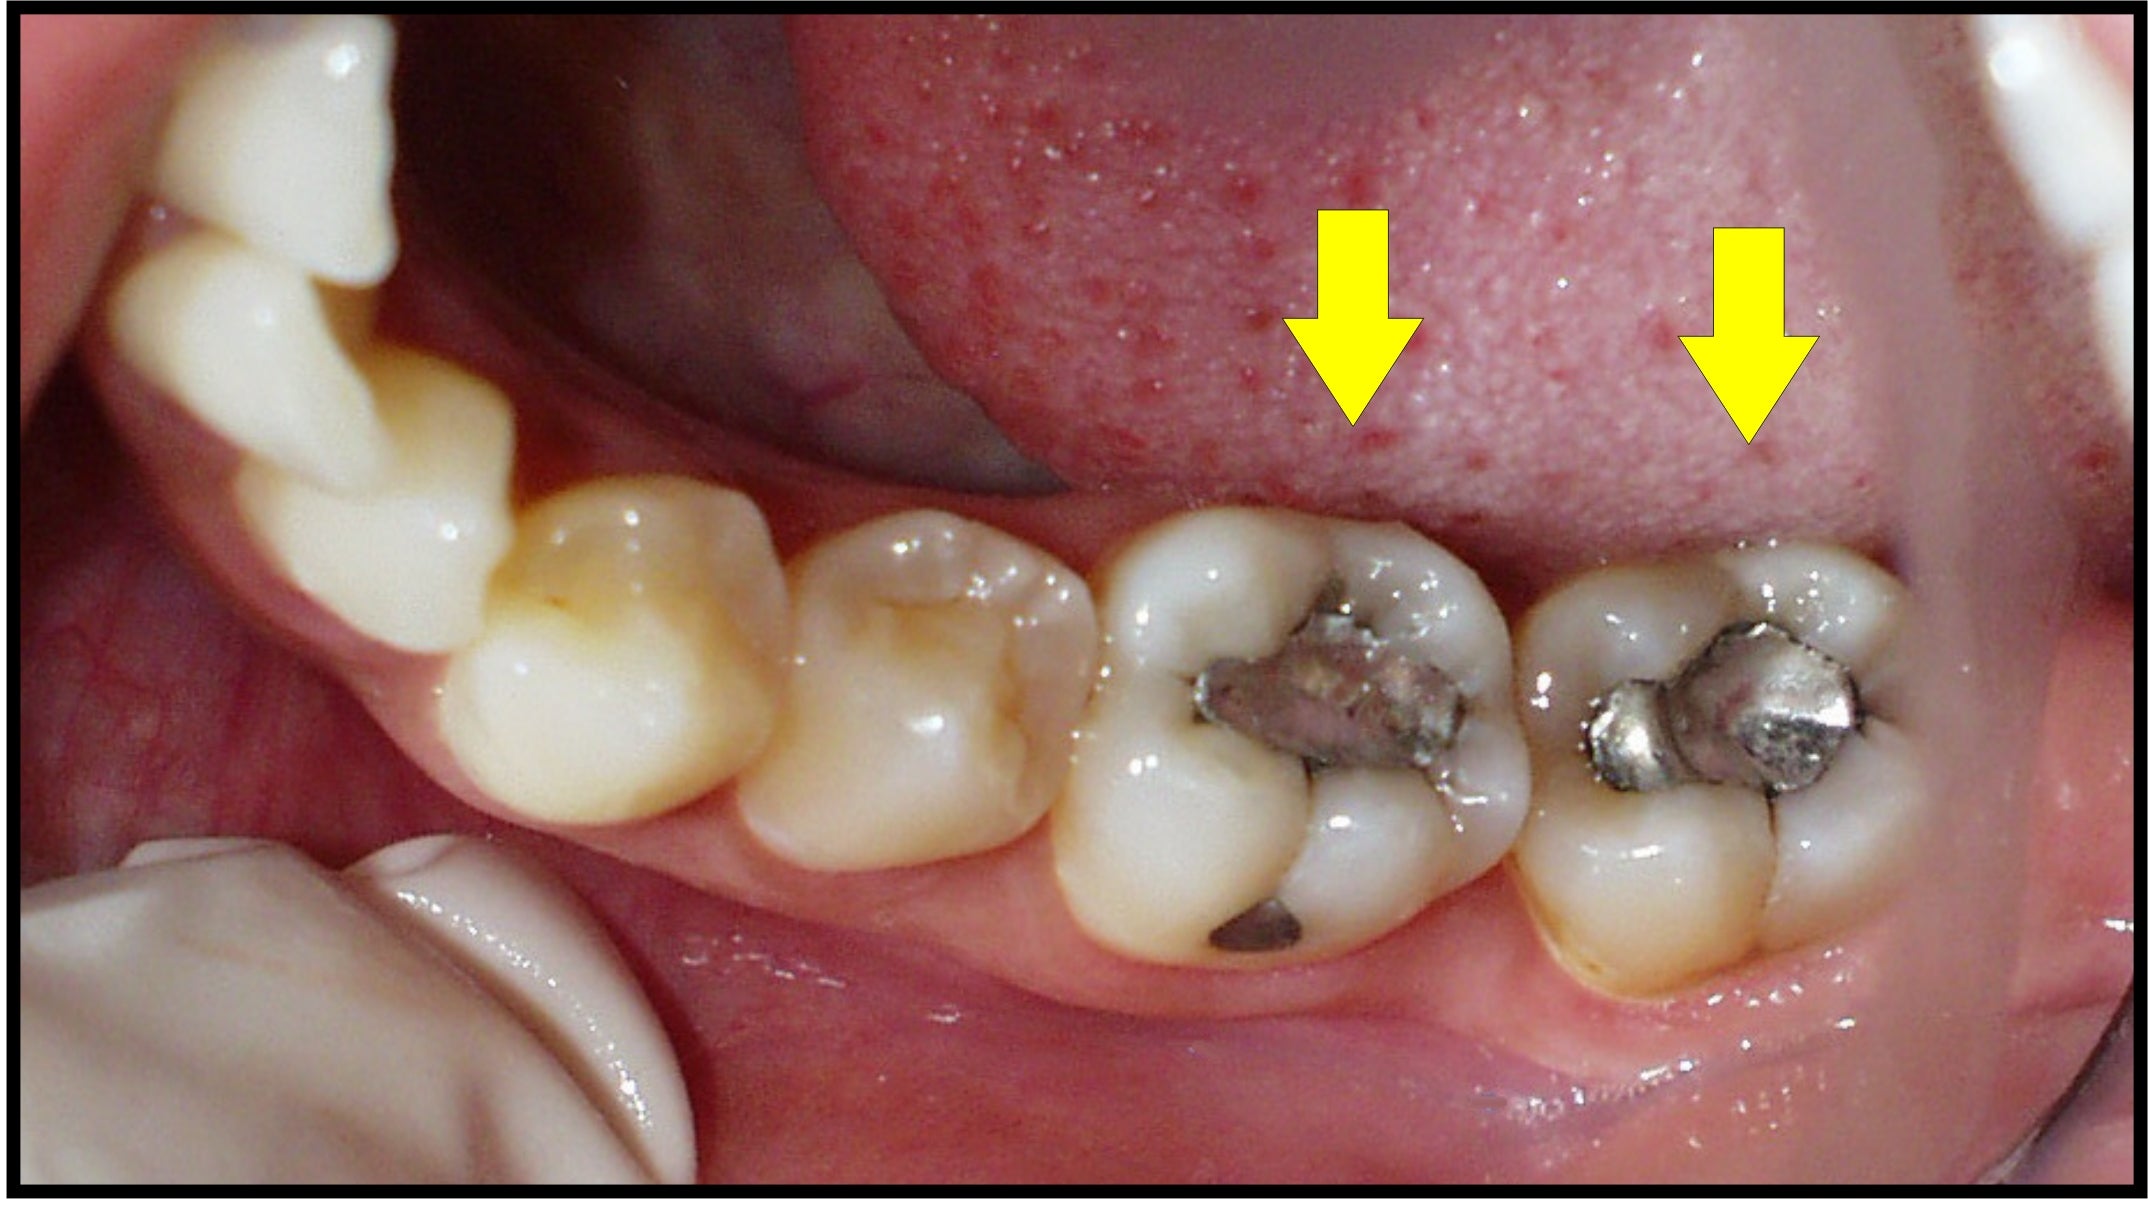

Tháng 6 năm 2008, FDA (Cơ quan Quản lý Thực phẩm và Thuốc Hoa Kỳ) đã thừa nhận rằng miếng trám bạc có thể không an toàn. Đến nay, cuối cùng cũng đã có thông tư về việc NGƯNG SỬ DỤNG AMALGAM TRONG NHA KHOA.